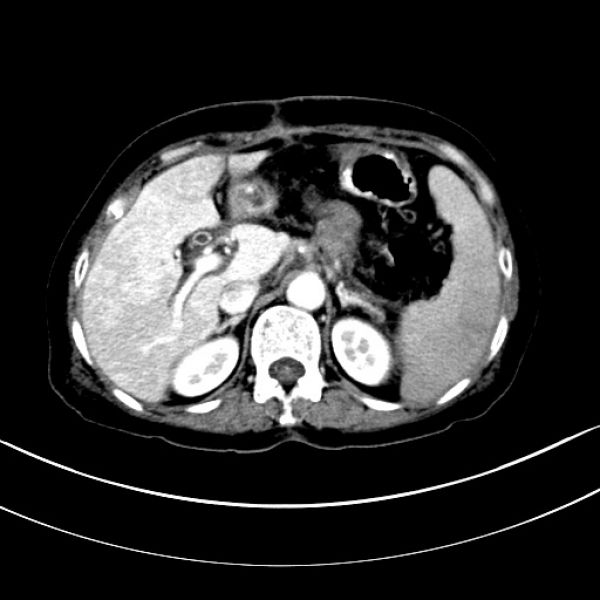

病人彭某某,61岁,因“体检发现胰腺占位1周”入住肝胆外科一病区,完善CT、MRI等影像学检查后,入院诊断为:胰颈部肿块,考虑胰腺癌,且周围血管侵犯可能性大。经科内讨论,认为患者胰腺颈部肿瘤局限,没有远处转移,一般情况良好,有手术指征和手术条件,加上患者及家属手术意愿强烈,可以实施手术。但该胰颈部肿瘤较大,最大径为5cm(T3期以上),该部位肿瘤常常累及背侧和头侧的血管,如背侧的肠系膜上静脉、脾静脉、门静脉,头侧的肝总动脉、腹腔动脉、脾动脉;一旦术中确认血管侵犯,为实现肿瘤的R0切除,则可能需要进行血管切除重建。在胰腺的切除范围上,有全胰腺切除和扩大的胰头十二指肠切除两种术式选择,全胰切除术后,胰腺的内、外分泌功能完全丧失,势必影响患者的生活质量,但是,决定是否能保留远端部分胰腺,还是取决于术中胰腺断端是否获得阴性切缘;患者的手术难度非常大,且术前带有诸多不确定性!

术前CT